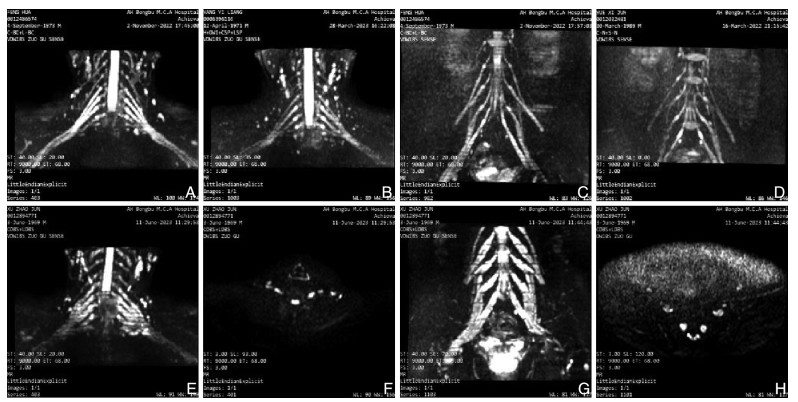

•   Objective  To explore the significance and mechanism of neuroultrasound and neuromagnetic resonance imaging in the diagnosis of Guillain-Barré syndrome (GBS).  Methods  A total of 43 GBS patients who were first diagnosed at the First Affiliated Hospital of Bengbu Medical University from October 2021 to February 2025 were enrolled, and 24 patients with normal physical examination were enrolled as control group. Based on neurophysiological examinations, the GBS were classified into two subtypes: acute inflammatory demyelinating polyneuropathy (AIDP) and acute motor axonal neuropathy (AMAN). Neuroultrasound and neuromagnetic resonance imaging were performed on all subjects. The cross-sectional area of the cervical nerve roots and peripheral nerves (CSA) was measured by neuroultrasound, and the CSA of the cervical nerve root and lumbar sacral nerve root was measured by neuromagnetic resonance imaging. The degree of neurological impairment in GBS was assessed using the GBS disability scale scores (GDSS), and the correlation between CSA values and the degree of neurological deficit was evaluated. Peripheral venous blood was collected, and the levels of pyroptosis-related inflammatory factors in peripheral blood were measured using ELISA.  Results  Compared with the control group, the nerve roots and peripheral nerves of the limbs in the AIDP group and the AMAN group were thickened, and the CSA value was increased. Among them, nerve ultrasound showed that there were statistically significant differences in C5 and C6 among the three groups (H=20.216, P < 0.001; H=12.452, P=0.002), and the magnetic resonance imaging results showed that compared with the AMAN group and the healthy control group, the CSA values of C4-C8 and L3-S1 in the AIDP group were significantly increased, and the differences were statistically significant (P < 0.01). The CSA value of peripheral nerves was positively correlated with the degree of neurological deficit (P < 0.05). Pyroptotic inflammatory factors were higher than those in the control group, and the difference was statistically significant (P < 0.05).  Conclusion  The elevated CSA values of nerve roots and peripheral nerves, as well as neurological deficits in GBS, may be associated with the inflammatory cascade triggered by pyroptosis pathway activation. The detection of peripheral blood inflammatory cytokines combined with neuroimaging may facilitate early diagnosis of GBS and provide novel insights for its clinical management.